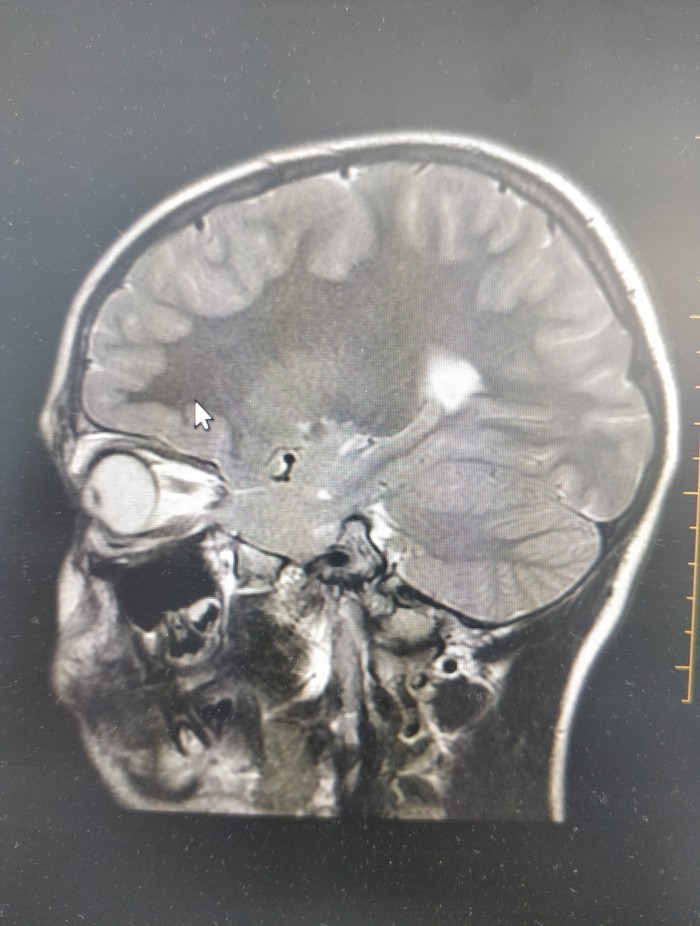

Картинки с яМРТ

Глянул на пост https://pikabu.ru/story/mrt_moego_litsa_5991718

решил тоже запилить)

1. Бойцы Mortal Combat

Артефакты от металлических конструкций на зубах.